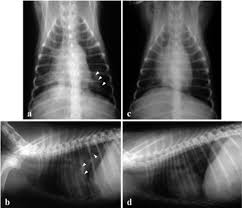

X rays are very helpful in the diagnosis of lung cancer in dogs. If you have lung cancer, it may be more difficult for your doctor to diagnose pneumonia. A white spot amidst the normal black lungs can therefore be a cancer, infection. Dog pneumonia or lung cancer. Pneumonia is a lung infection that leads to breathing difficulties and fluid in the lungs.

A definitive diagnosis of lung cancer requires a sample of tissue (biopsy). X rays are very helpful in the diagnosis of lung cancer in dogs. Primary lung cancer are frequently located in the caudal (towards the hind end of the pet) lung lobes, however can be located in any lung lobe and are usually a single mass in the lungs, unless the tumor has spread. If your dog has a chronic cough, you'll need to rule these out. The first of these possibilities could be investigated by bronchoscopy. A definitive diagnosis of lung cancer requires a sample of tissue (biopsy). The second kind of lung cancer in dogs is called metastatic lung cancer, which means the cancer originated somewhere else in the body, but has spread to the lung. Bacterial pneumonia is an inflammation of the lung usually caused by bacterial or viral infection but can be caused by inhalation of an irritant. The respiratory system consists of the large and small airways and the lungs. Lung cancer is actually the number one killer when it comes to cancers. But in some rare cases, it may be a lung cancer (primary or secondary). In both cases, you may have. Typical signs of bacterial pneumonia include fever, difficulty breathing, lethargy and coughing.

Deep Convolutional Neural Network With Transfer Learning For Detecting Pneumonia On Chest X Rays Springerlink from media.springernature.com Often, people with recurrent bouts of pneumonia tend to have unidentified lung cancer that can progress to advanced stages without appropriate treatment. A white spot amidst the normal black lungs can therefore be a cancer, infection. Here's why cancer can look like an infection: Persistent chest infections can be signs of something more serious than pneumonia, and unfortunately, it. A retrospective study of 1011 hospitalized patients with pneumonia was undertaken to assess the value of routine convalescent chest radiography for detection of underlying lung cancer. The first of these possibilities could be investigated by bronchoscopy. But the pneumonia density can obscure, or be distal to a cancer. Typical signs of bacterial pneumonia include fever, difficulty breathing, lethargy and coughing.